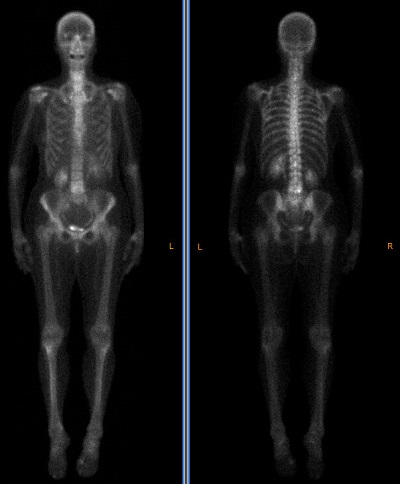

NM Whole Body

NM Processing Application Suite provides a comprehensive analysis, and processing environment for Planar and SPECT studies. The Planar suite includes Renal, Lung, Whole Body and bone, Cardiac (MUGA), Esophagus, Gastro Intestinal and Hepatobiliary applications.